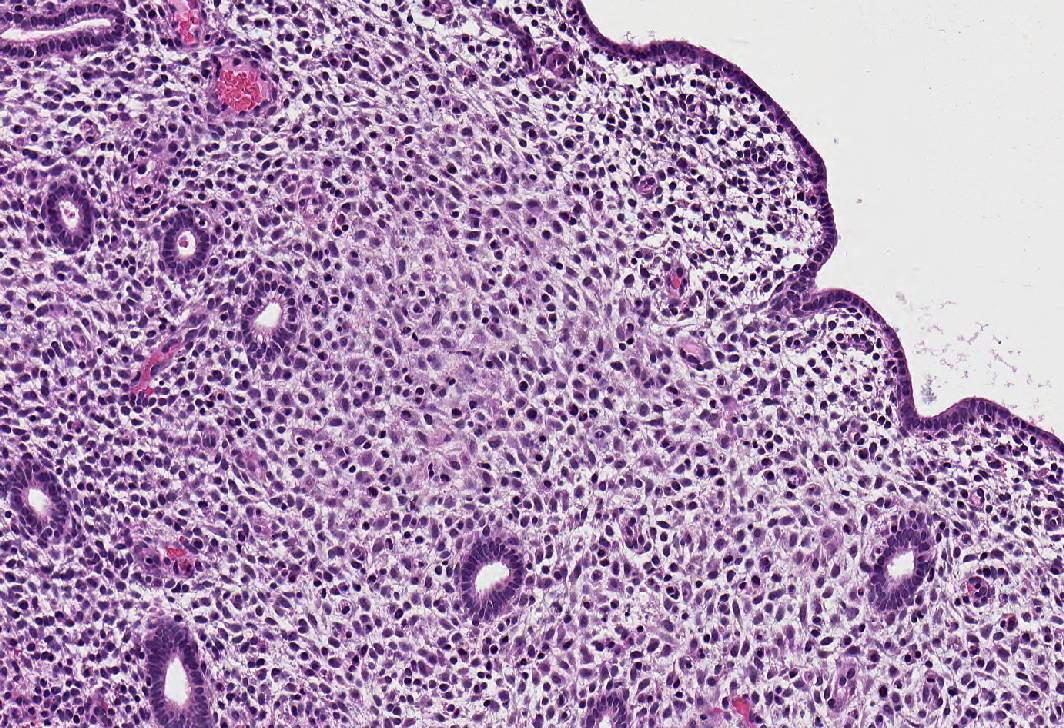

- Combined:

- Widely spaced, narrow, straight glands lined by cuboidal epithelial cells lacking nuclear pseudostratification or mitotic activity

- Sparsely cellular pseudodecidualized stroma

- Thin walled, ectatic stromal vessels, sometimes with thrombi

A 32 year old woman has been on a combined oral contraceptive for 2 years. Which of the following statements is true regarding morphologic changes seen in her endometrial biopsy?

- Widely spaced, narrow, straight glands lined by inactive endometrium and pseudodecidualized stroma, consistent with changes associated with combined oral contraceptives

D. Widely spaced, narrow, straight glands lined by inactive endometrium and pseudodecidualized stroma, consistent with changes associated with combined oral contraceptives